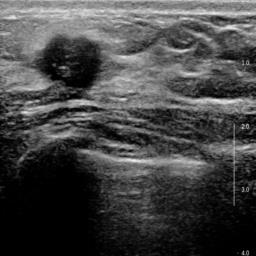

Ultrasonography is an important routine examination for breast cancer diagnosis, due to its non-invasive, radiation-free and low-cost properties. However, it is still not the first-line screening test for breast cancer due to its inherent limitations. It would be a tremendous success if we can precisely diagnose breast cancer by breast ultrasound images (BUS). Many learning-based computer-aided diagnostic methods have been proposed to achieve breast cancer diagnosis/lesion classification. However, most of them require a pre-define ROI and then classify the lesion inside the ROI. Conventional classification backbones, such as VGG16 and ResNet50, can achieve promising classification results with no ROI requirement. But these models lack interpretability, thus restricting their use in clinical practice. In this study, we propose a novel ROI-free model for breast cancer diagnosis in ultrasound images with interpretable feature representations. We leverage the anatomical prior knowledge that malignant and benign tumors have different spatial relationships between different tissue layers, and propose a HoVer-Transformer to formulate this prior knowledge. The proposed HoVer-Trans block extracts the inter- and intra-layer spatial information horizontally and vertically. We conduct and release an open dataset GDPH&GYFYY for breast cancer diagnosis in BUS. The proposed model is evaluated in three datasets by comparing with four CNN-based models and two vision transformer models via a five-fold cross validation. It achieves state-of-the-art classification performance with the best model interpretability.